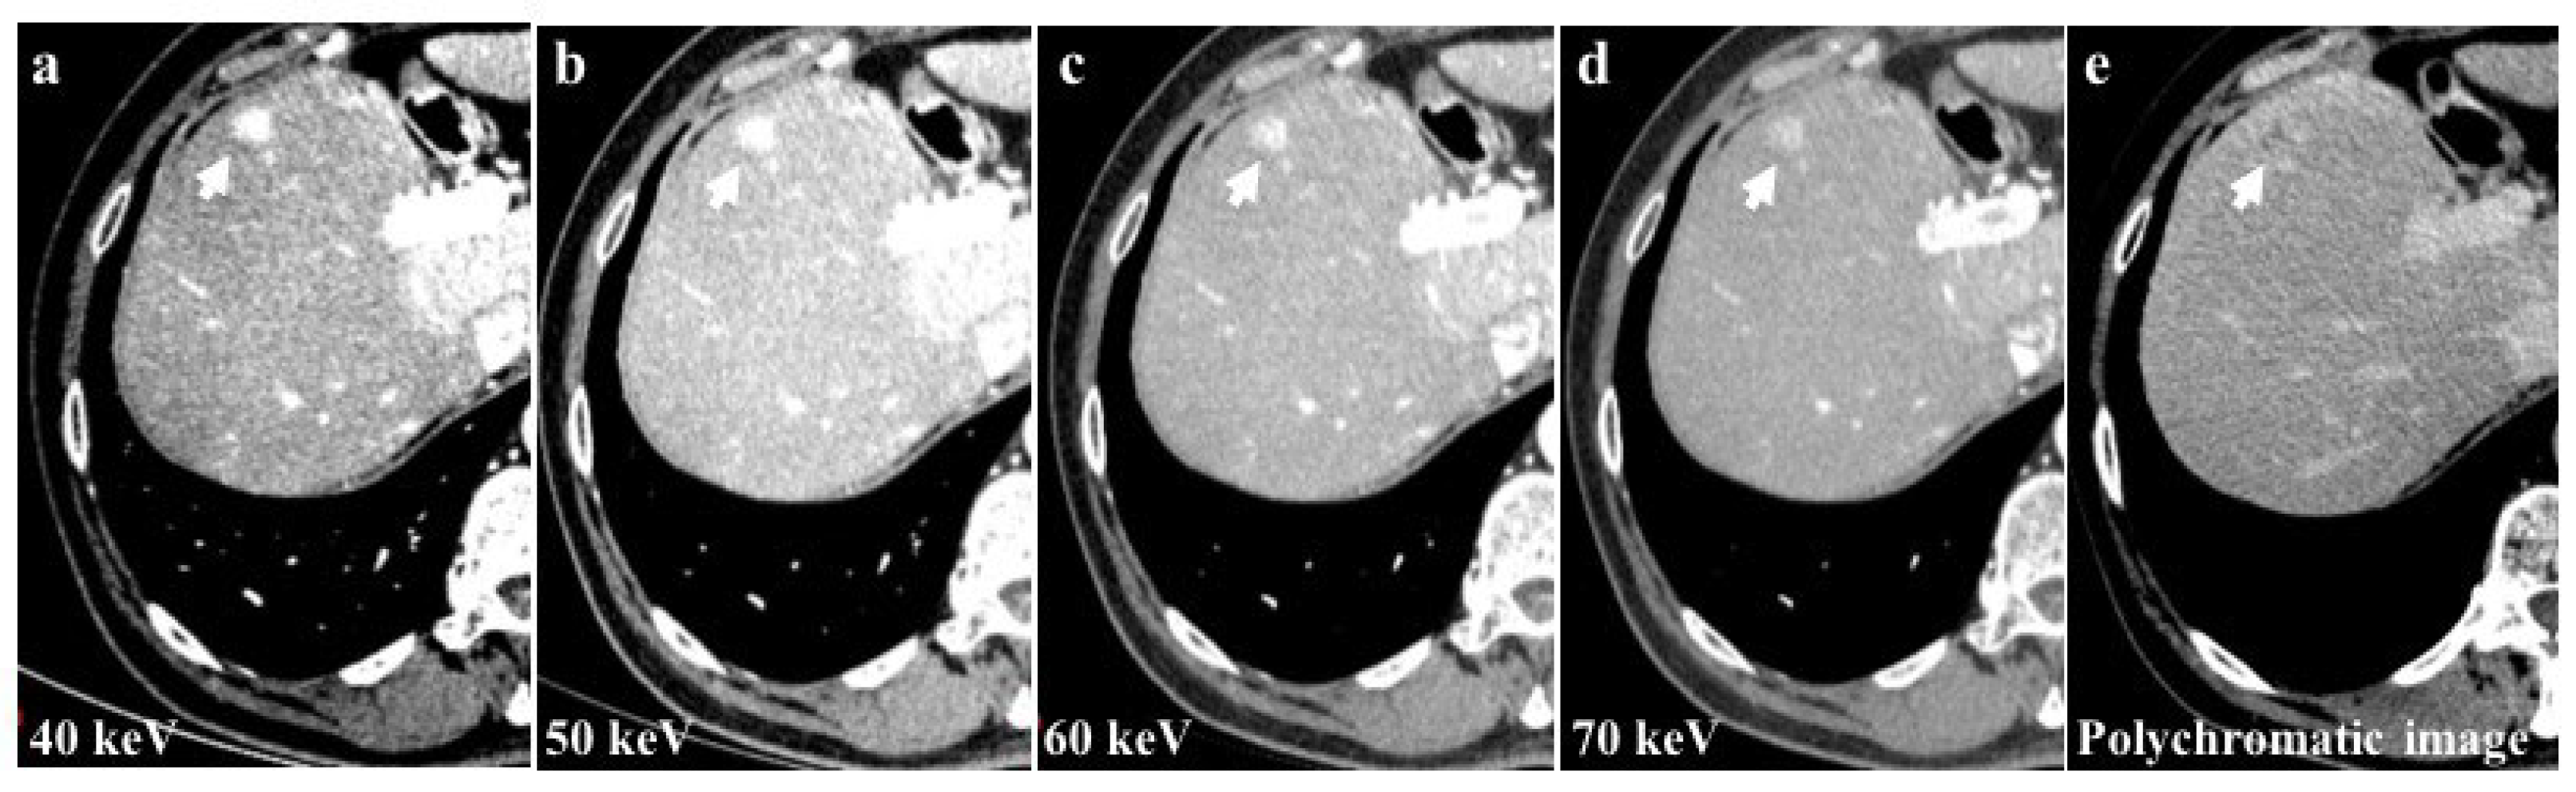

Among the examined study examinations, the 40 keV images exhibit the highest CM attenuation when compared to the 50 keV, 60 keV, and 70 keV images. Moreover, the 40 keV images demonstrate the most pronounced enhancement of vascular structures and parenchyma (Figure 4).

Figure 4.

The 40 keV images of a 56-year-old patient with hepatocellular carcinoma (HCC) of the 8th liver segment (a) showed a higher contrast media attenuation and the highest difference between the background parenchymal and the lesion enhancement (arrows) compared to 50 keV (b), 60 keV (c), and 70 keV (d) image reconstructions. Monochromatic energy levels (40–70 keV) also increase the detectability of small HCCs and cirrhotic liver disease when compared to conventional polychromatic imaging (e).